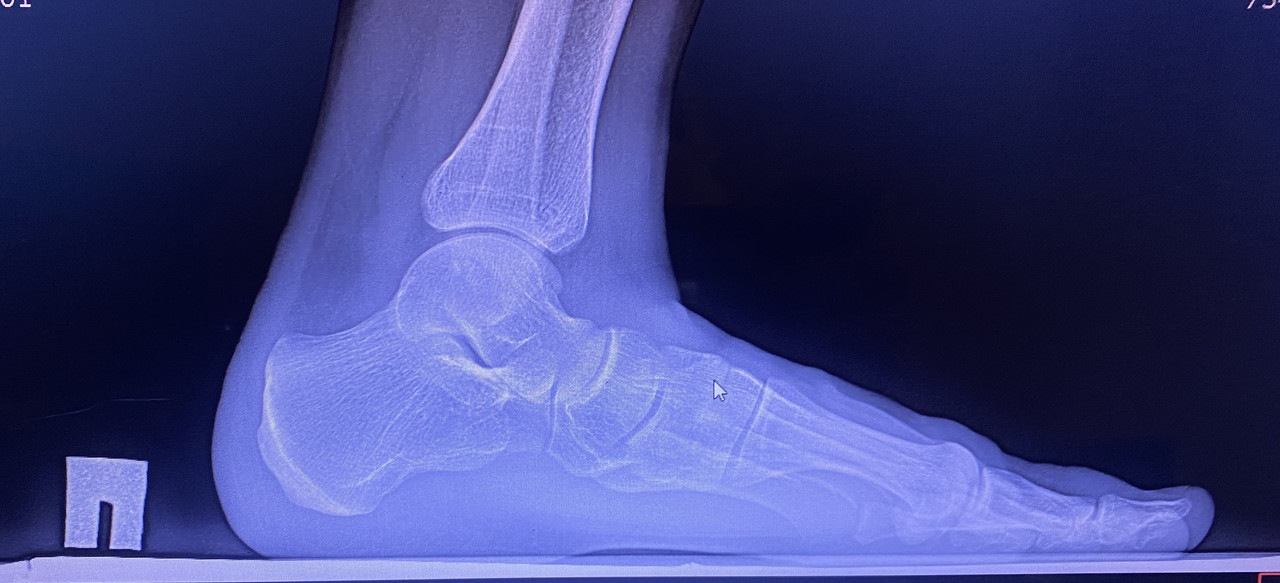

Здравствуйте, я сделал рентген стоп с нагрузкой, для определения степени продольной плоскостопии, по направлению от военкомата. В заключении написано, что на правой ноге у меня 3ст плоскостопии 158 градусов. Во время снимка я сгибал ногу в колене, поскольку это позволяет мне создать большую нагрузку для стопы. В интернете я слышал информацию, что подобные снимки военкомат считает выполненными неправильными, так ли это на самом деле?

Фото снимков приложил. spacer.png

При правильной укладке стопы для боковой проекции должна быть видна вся стопа с примерно 2 см дистального отдела малоберцовой и большеберцовой костей. Бедренная кость должна быть перпендикулярна к плоскости опоры. Дистальный отдел малоберцовой кости должен быть виден через заднюю сторону (половину) большеберцовой кости, а подошвенные поверхности головок плюсневых костей должны накладываться друг на друга при отсутствии ротации ступни.

У Вас на снимке укладка не корректная, поэтому в военном комиссариате могут направить на повторное исследование.